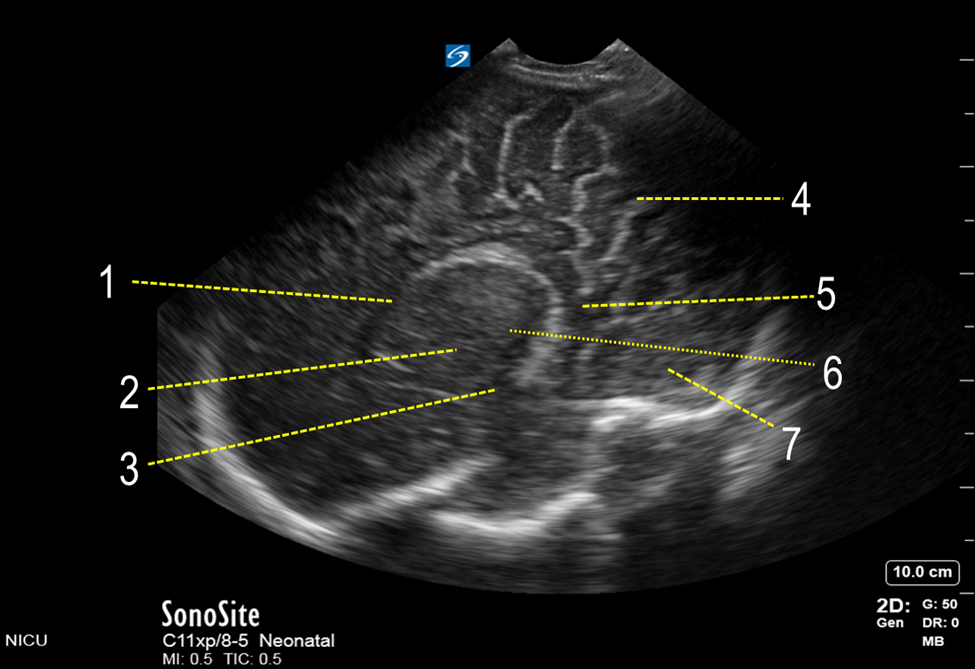

Neonatology Posterior Fontanelle Para-Sagittal View Image

1. Body of Lateral Ventricle

2. Basal Ganglia

3. Temporal Horn of Lateral Ventricle

4. Parietal Lobe

5. Occipital Horn of Lateral Ventricle

6. Thalamus Calcarine Fissure

7. Occipital Lobe